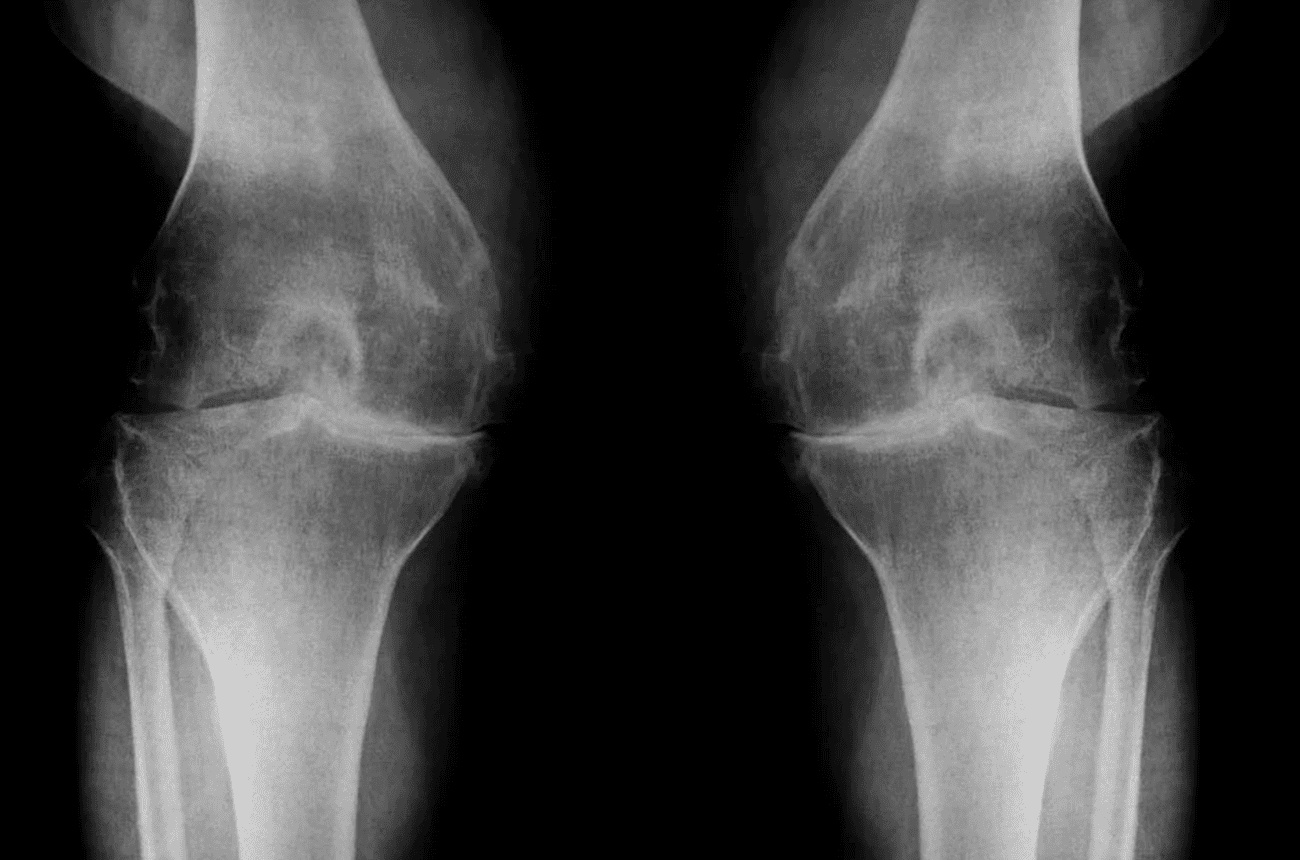

El diagnóstico se basa en la historia clínica y una evaluación física detallada. Las radiografías confirman el desgaste articular, y en casos específicos se emplean ecografía o resonancia magnética para evaluar la severidad y planificar el tratamiento más adecuado.